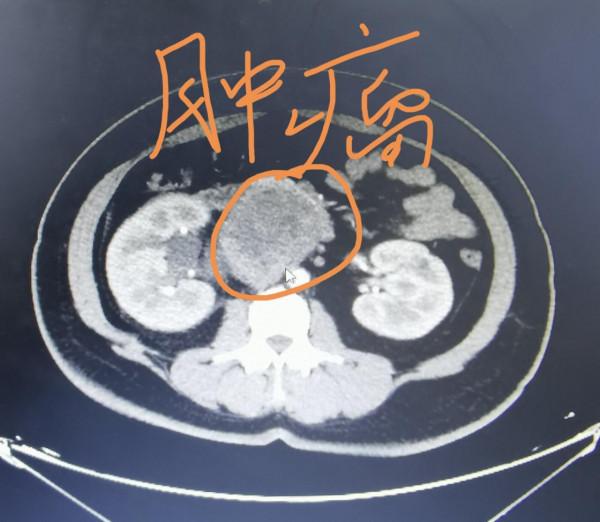

這兩天我去泌尿外科參加了一個多學科專家會診,這位患者是一位42歲的女教師,她在20多天前,覺得右側腰部肉皮絲絲拉拉的疼,在家附近的中醫館,進行了拔罐按摩以及拍打治療。進行了這些治療之後的幾天,有一天傍晚,覺得右側腰腹部疼的非常嚴重,她老公說,咱趕緊去大醫院吧,在老公的陪伴下,到了我們醫院急症就診,發現了腹腔有一個將近10釐米的腫瘤,就收到了泌尿外科住院。之所以請我會診,是泌尿外科在住院之後,又給安排了一個胸部CT檢查,發現了雙肺大小不等多發的結節,我會診看片子,考慮轉移可能的大。

我在病房裡見到了這位患者,問她這兩年有沒有查體?她說每年單位都組織,但這兩年自己因為疫情的原因,就沒有跟著去體檢機構查體。會診的時候,我們幾位專家討論,腹腔10釐米的腫瘤,這兩年體檢做腹部彩超,應該就能在小的時候發現。再次提醒各位朋友,單位組織的體檢是比較重要的,沒有任何症狀也要跟著去。